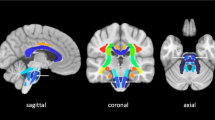

The lesion’s laterality was flipped to aligned ipsilesional and contralesional CST. Using a coronal view of FA color maps, 15 mask/regions of interest (ROI) were drawn across both ipsilesional and contralesional CST, 15 mm apart, originating from pons to cortex at V1 and V2 follow-up MRI as shown in Fig 2 C and Fig 2D. A centroid (i.e., the median of the volume at three intersecting coordinates) of each mask was computed. A control dataset was simulated using the contralesional CST centroid and mirrored to the ipsilesional hemisphere, which was used as the reference shape. For quality assurance, we also compared the centroid displacement using the contralesional CST and a white matter atlas CST template. Overall, using 3-dimensional measurements of the included patients, three sets of data, and 30 coordinates used to define the CST shape in each patient, a total of 9,450 data points were created. The coordinates of the shape were determined via centroid and are referred to as landmarks. The landmark configuration of all patients was subjected to a GPA.

Temporal changes in the hematomal tissues and corticospinal tracts (CST) in a representative patient are shown. A significant (p < 0.01) reduction in the hematoma volume between visit-1 (A) and visit-2 (B) is shown on a coronal view of a fluid-attenuated inversion recovery. The temporal change in the CST is illustrated by DTI color-coded maps at visit-1 (C) and visit-2 (D). Using principal component analysis, an overall change in the ipsilesional and contralesional CST shape is depicted in (E) using color code landmarks. At visit-1, the ipsilesional CST (red) shape was significantly (p < 0.0001) different in shape than the reference mirrored contralesional (green) shape. At visit − 2 (blue), the ipsilesional CST exhibited no significant difference as compared to the reference CST shape

Fig-2 A and Fig-2B demonstrate a significant reduction (16.37 ± 27.28 to 3.63 ± 5.01 cc, p < 0.0001) in hematoma volume and temporal change in the ipsilesional CST shape between the two time points after the ICH. Fig-2 C and Fig-2D are DTI color maps showing the deformation and restoration of the ipsilesional CST shape (superior-inferior blue fiber bundle) at baseline and after three months, respectively. The temporal deformation of the ipsilesional CST shape coordinate among all patients is summarized inFig-2E. Compared to the contralesional CST, the baseline ipsilesional landmarks (red dots) were displaced or deformed as illustrated; however, over time, the CST shape was restored (blue dots) to its pre-ICH location. No significant deformation was noted in the control (green dots) contralesional CST over time.

Fig 3 A illustrates the shape change in individual participants’ ipsilesional CST over time in the first three principal spatial component scores. The reference shape (contralesional CST) is shown in green, where the coordinates were more closely superimposed with minimal distance between the coordinates. At the V1, the ipsilesional CST shape’s coordinates were more dispersed with larger distances, and minimal superimpose as compared to the reference shape, as shown in Fig 3A (red). At the V2, the ipsilesional shapes were much closer to each other and better superimposed with the reference shape and with no significant difference between them.

Illustrates the temporal changes in ipsilesional CST shape variance in the first three principal components (P1, PC2, and PC3). Using Kendall’s shape space, after principal components analysis, the Procrustes coordinate landmarks are represented as a single point in a multidimensional space. The distance between any given point represents the magnitude of the difference in shape. A illustrates the change in ipsilesional CST shape variance in the PC1, PC2, and PC3 at visit-1 (red) and visit-2 (blue) as compared to the reference shape (green). Fig-A illustrates the change in ipsilesional CST shape variance in the PC1, PC2, and PC3 at visit-1 (red) and visit-2 (blue), as compared to the reference shape (green). The ipsilesional CST shape variance was 58.3% among the first three principal components’ scores variance. As compared to the reference shape, the baseline shape exhibits significant differences, which were restored at the follow-up imaging. The box plots in B are a quantitative summary of shape variance in the first three PCs with significant (p < 0.001) differences in PC1 at the baseline variance shape variance in PC1